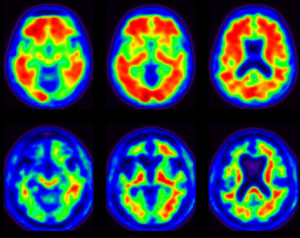

When the second neurologist examined Larry, he helped him join the Imaging Dementia – Evidence for Amyloid Scanning (IDEAS) Study. The goal of the trial is to see if using positron emission tomography (PET) imaging as a diagnostic tool leads to changes in disease management. The Centers for Medicare and Medicaid Services is paying for scans for those in the study.

After finishing the tests, the second neurologist diagnosed Larry with mild cognitive impairment (MCI). When the neurologist asked Larry how he felt about the diagnosis and the positive PET scan result, Larry responded that he was “a little relieved” to finally know what was causing the changes.